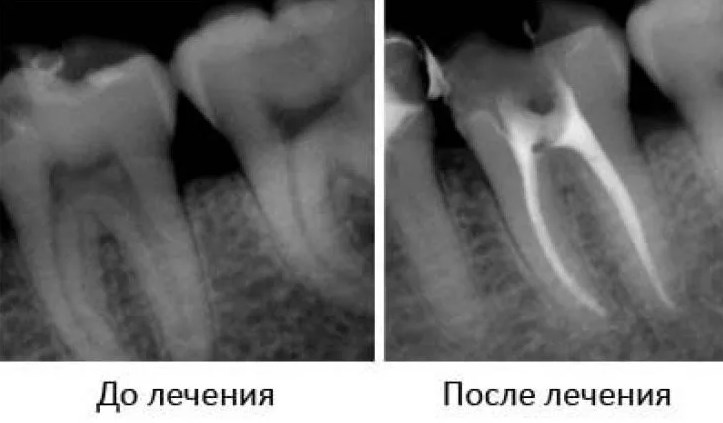

Рентгеновские или цифровые снимки доступны для контроля наличия пустот в корнях депульпированного зуба. Перед лечением рентгеновское изображение помогает определить форму и количество корней в молярах. Обычно боковые моляры имеют сложные и глубокие корни. Поэтому рентгеновский снимок зуба делается дважды — перед началом и после окончания пломбирования каналов.

На этих фото — рентгеновские снимки корней. Пломбировочный материал в зубе и корнях выглядит как сплошной белый цвет.